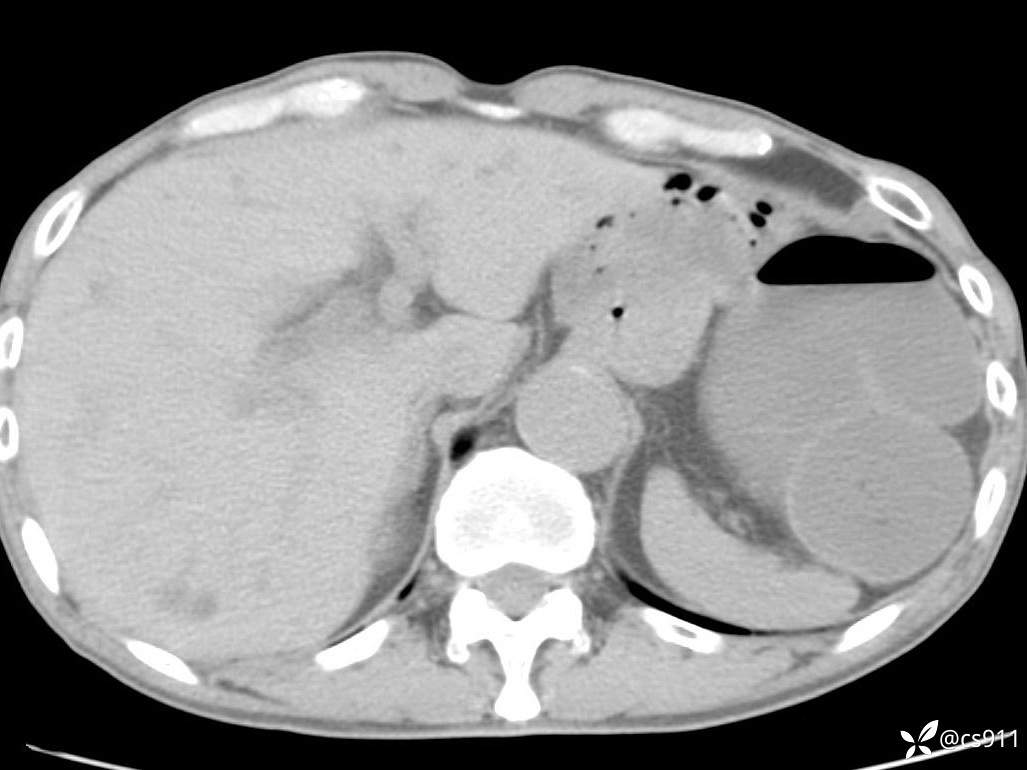

急腹症之急诊CT,原因?答案公布

男,77岁,腹痛、腹胀伴恶心呕吐1天。呕吐胃内容物,非喷射性呕吐,有咖啡色样胃内容物,诉有胃穿孔病史。查体:全腹平,下腹部压痛,全腹无反跳痛,叩诊呈浊音,移动性浊音阴性,肠鸣音减弱,1-2次/分。肛检:直肠未扪及明显肿物,可触及大量粪块。

T 36.6℃ P 80次/分 R 26次/分 BP 100/60mmHg

白细胞(WBC) H 14.55 10e9/L 4-10

中性粒细胞百分率(NEUT%) H 85.7 % 40-75

血淀粉酶(AMY) HH 1859 U/L 35-135

癌胚抗原(CEA) H 27.44 ng/ml 0-5

呕吐物 潜血试验 * 阳性 阴性

患者轮椅入室检查神志清楚, 能配合摆位和呼吸